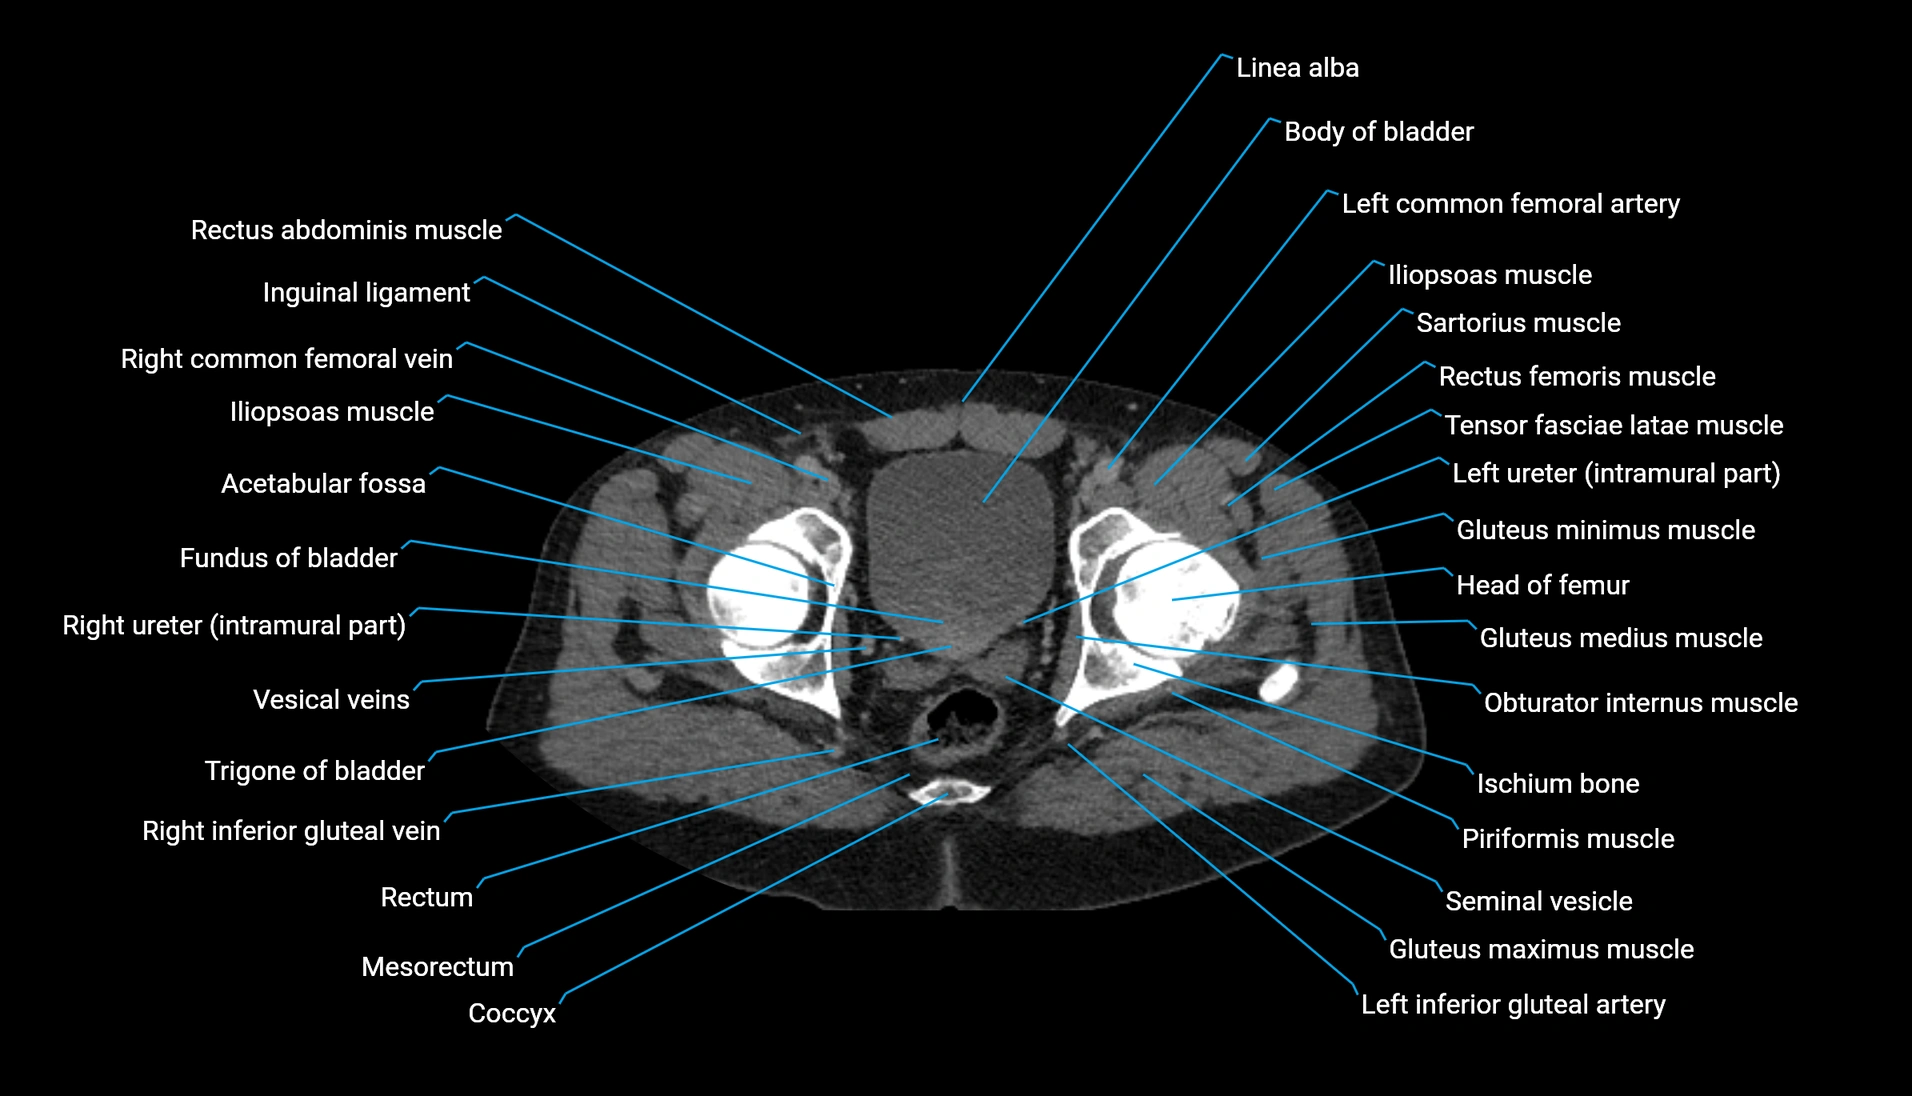

CT Appearance

Non-contrast CT:

-

Demonstrates cortical bone of acetabular rim in excellent detail

Detects fractures, dysplasia, retroversion, or bony overcoverage (pincer impingement)

3D reconstructions used in preoperative hip surgery planning

CT image